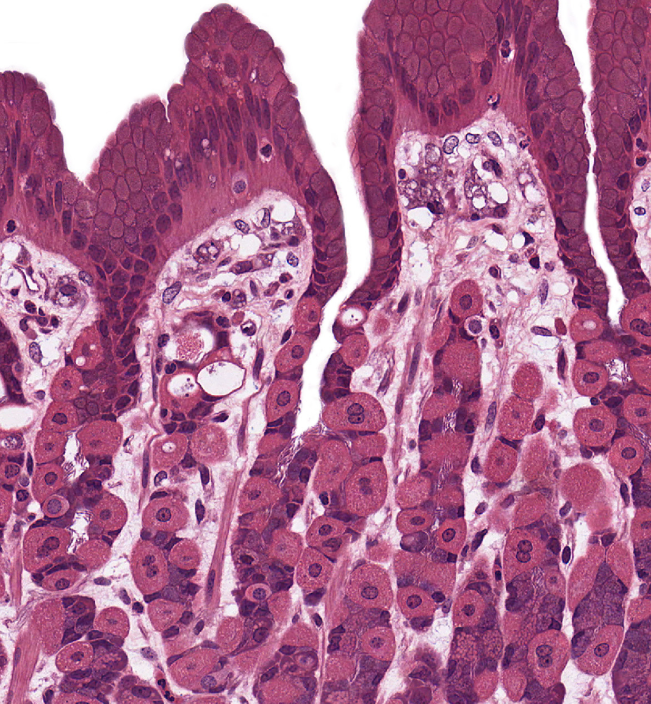

Small Intestine

NOTICE: THE FINGER-LIKE PROJECTIONS (VILLI) WITH OPEN SPACE INSIDE AND A FEW GRAY/BLUE GOBLET CELLS ALONG THE SIDES (NOT AS MANY AS LARGE INTESTINE